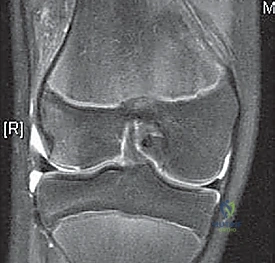

- MRI Scan: Highly recommended for all patients with a large traumatic effusion due to the high rate of occult articular or osteoarticular injury.

* Osteochondral Lesions: Crucial for determining size, location, and potential for repair versus removal.

* Bone Bruise Pattern: Confirms patellar dislocation (medial patella and lateral femoral condyle).

* Anatomical Risk Factors: Assesses patella alta, trochlear dysplasia, tibial tubercle-trochlear groove (TT-TG) distance.

* Bone Bruises: MRI often reveals increased signal on the medial patella and the midportion of the lateral femoral condyle. This distinct pattern helps differentiate it from ACL tears.